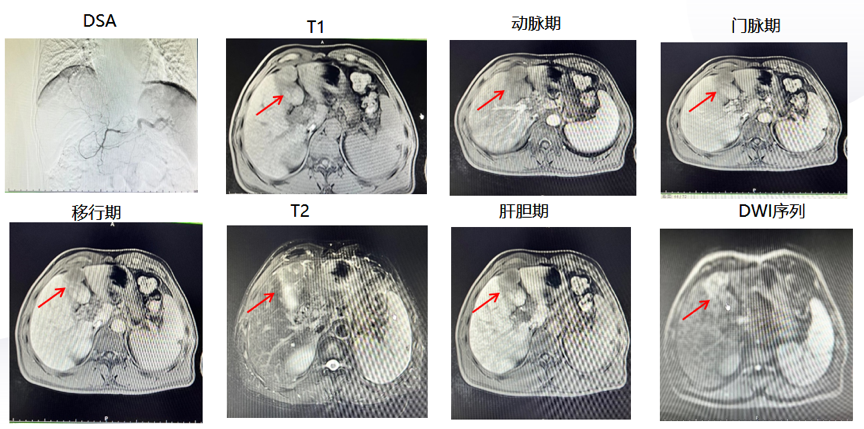

2021年8月,腹部普美显增强MRI:肝左叶(S2-4)多发肝癌灶范围较前减小,门静脉主干及门静脉左右支癌栓较前增多,腹膜后多发小结节,转移待除外(图2)。给予TACE 瑞戈非尼 卡瑞利珠单抗治疗。

2021年12月,腹部普美显增强MRI:治疗术后改变,未见明显肿瘤活性,门静脉主干及门静脉左右支癌栓较前减小,腹膜后多发小结节(图2)。

图2.2021年5月、2021年8月、2021年12月复查增强MRI

2022年5月再次行TACE治疗,MRI和TACE中均未见明显肿瘤活性,且MRI示门静脉主干及门静脉左右支癌栓较前减小(图3)。

图3.2022年5月复查MRI